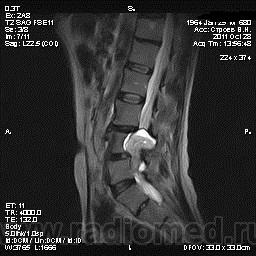

Жалобы на боли в пояснице постоянного характера, исследование началось после приема обезболивающего препарата, предоставлены выписки после неоднократного лечения в стационаре с диагнозом: Полисегментарный остеохондроз, деформирующий спондилез, грыжа диска L4-5, протрузия диска L3-4, умеренно выраженный болевой синдром.

От оперативного лечения отказался по поводу эпиприступов в анамнезе.

По структуре и локализации образование, вероятно, исходящее из корешков спинного мозга. Как у него с тазовыми функциями?

То что видно -слишком гомогенный сигнал для дермоида. Учитывая деформацию костных структур- заболевание существует давно. И не забыть внимательно посмотреть на предмет spina bifida, может это вообще грыжа. Контрастику бы налить.

я за невриному , структура гомогенная , а дермоид , неоднороден и выглядит как "губка", то есть с мелкими очагами повышенного мр-сигнала в Т2. по- моему...

вообще то забираю свои слова обратно (не согласна с невриномой) ... одолели сомнения.. там кажется есть кистозный компонент , отличный от сигнала спинномозговой жидкости . гистология покажет ))

Кистозный компонент не исключает невриному.

в литературе говорится что экскавация или продавливание задней поверхности позвонка- тоже характерная черта роста неврином в этой локализации.